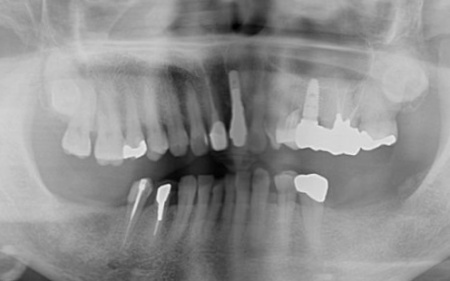

70代女性 歯根が折れた左上奥歯を抜いてインプラント治療で噛み合わせを回復した症例

拝見したところ、左上奥歯2本(第1小臼歯、第2小臼歯)の被せ物が外れていたため、レントゲン撮影で詳しく検査をした結果、歯根が折れていることが確認できました。

また、以前歯の神経を除去する根管治療を受けたそうですが、その際に使用された細い器具 (リーマー)の破片が根管内に残っています。

さらに、歯の周囲にある歯周ポケットの深さを測定したところ、口蓋側(上顎の内側)は歯根の先端まで達していました。

これでは、再度根管治療を行っても歯茎の状態が改善する可能性は低いと考えられます。

このまま放置すると周囲の骨や歯茎に炎症が広がるリスクがあるため、早急に適切な治療をする必要があると診断しました。